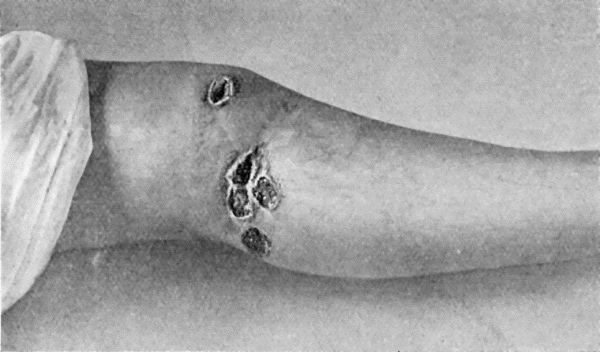

35.Tuberculous Sinus injected through its opening in the Forearm with Bismuth Paste 144

126.Diffuse Tuberculous Osteomyelitis of Right Tibia 458